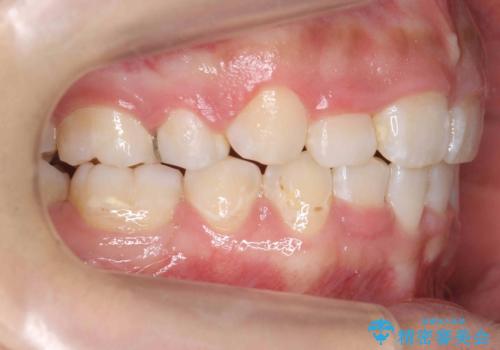

前歯のがたがた 前歯が内側に傾いている

- 前歯のがたがたを主訴に来院。

上の歯並びが前にずれて、さらに前歯が内側に倒れて過蓋咬合を呈していました。

奥歯のかみ合わせもずれていたため、上の奥歯を後ろに下げる処置をミニスクリューを用いて行いました。